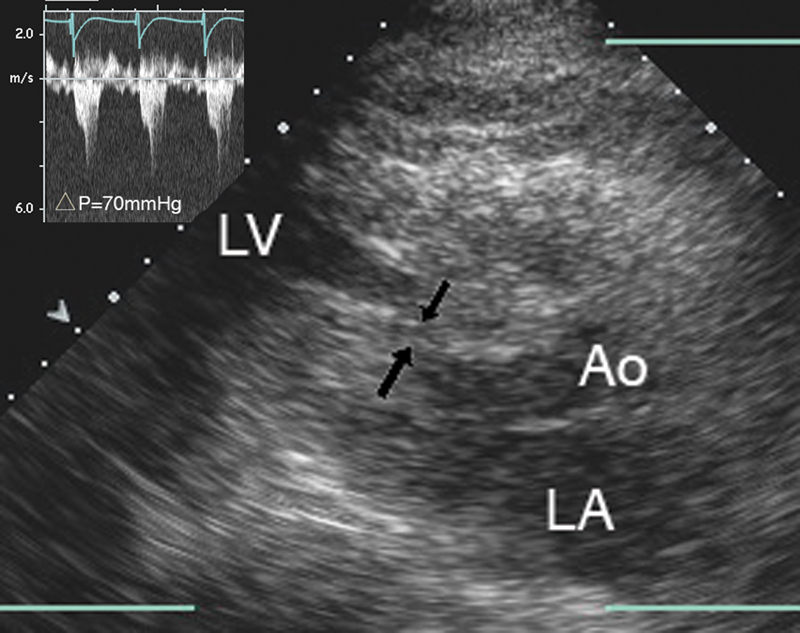

فحوصات تشخيصية لبعض امراض القلب والشرايين التاجية